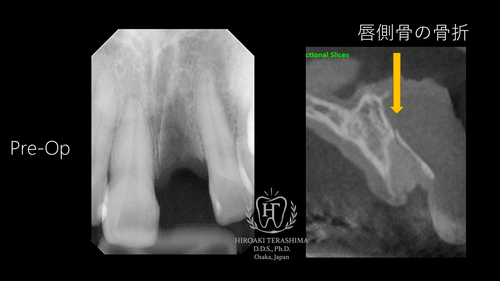

52歳・女性。 外傷により、左上の前歯(1番)が完全脱臼。 受傷から約1か月後、「インプラントは難しい」と言われたものの、当院の症例集をご覧になり来院されました。来院時は歯が完全に無い状態でした。

術前の状態と問題点

CT検査では、唇側の骨は形としては残存しかし骨折しており、吸収が進行寸前でした。このまま時間が経過すると骨が吸収し、それに伴い歯ぐきも陥没するため、時間が経てば経つほど審美的な回復が非常に困難となる状態でした。